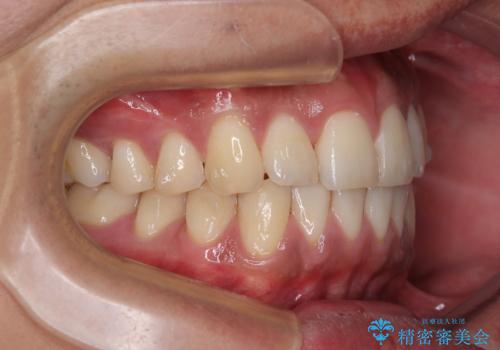

診察したところ、上下顎前歯部に軽度の叢生(ガタつき)が認められます。

目立たない装置を希望されたのでインビザライン ライトパッケージで治療を行うことになりました。